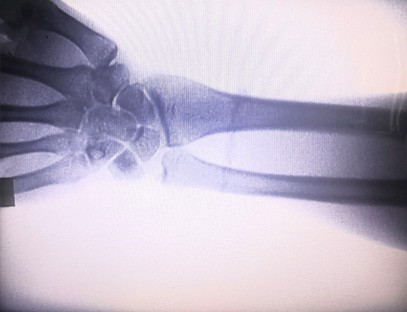

Mesin X-ray mudah alihialah dos sinaran yang rendah, instrumen mudah alih yang sangat selamat yang boleh mendapatkan imej berkualiti tinggi sambil mengurangkan pendedahan sinaran. Ia mengimbangi kekurangan peralatan hospital yang besar dan boleh dipindahkan dan dibawa ke mana-mana pada bila-bila masa. Terutamanya sesuai untuk unit dan individu yang mempunyai bajet yang tidak mencukupi dan keperluan yang rendah untuk imej. Mesin X-ray generasi baharu kami dilengkapi dengan skrin besar definisi tinggi 10 inci, yang mempunyai julat sudut tontonan yang lebih besar dan boleh melihat sepenuhnya melalui seluruh tapak tangan, termasuk patah tulang, terkehel, arthritis dan tumor tulang. Ia boleh disambungkan kepada pencetak filem untuk mencetak filem ortopedik, dan juga boleh digunakan untuk pengeluaran dan ujian perindustrian. Tidak memerlukan bilik gelap, perspektif langsung, pemerhatian masa nyata. Mesin ini mempunyai sistem pengimejan resolusi tinggi yang boleh menangkap imej mana-mana struktur tulang dengan sangat jelas. Untuk menyediakan peralatan dan penyelesaian ujian X-ray terbaik untuk pengilang perubatan, haiwan peliharaan, industri, produk elektronik, jabatan pemeriksaan dan penyelenggaraan serta makmal penyelidikan.

Pengkhususan:Direka bentuk untuk keperluan klinik ortopedik, terutamanya sesuai untukPengimejan sinar-Xanggota badan seperti tangan, pergelangan tangan, siku, bahu, lutut, buku lali, dll.

Pengimejan yang jelas:Teknologi pengimejan digital termaju digunakan untuk menyediakan imej X-ray berkualiti tinggi, membantu doktor mendiagnosis keadaan dengan tepat.